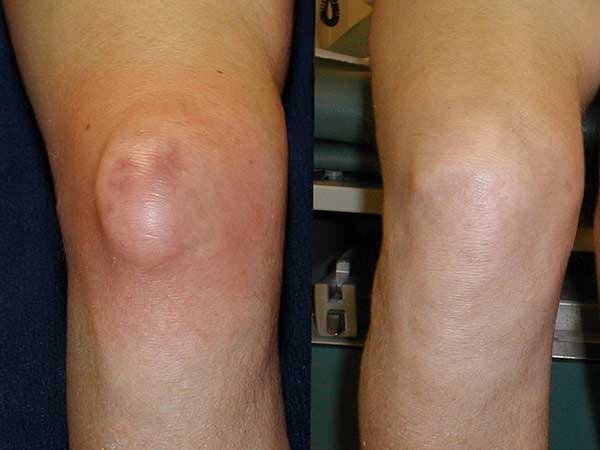

Hasil pengobatan lutut.